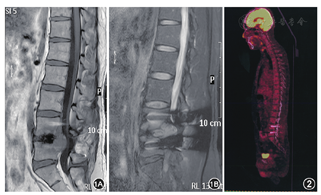

患者 男性35岁,右利手。因"发现椎管内占位2年伴左下肢胀痛3个月"于2015年12月16日入住吉林大学第一医院。患者2年前因腰椎间盘突出在当地医院行腰椎内固定,术中发现椎管内占位,因当地医院条件限制未行肿物切除。体检:全身皮肤黏膜无黑色素痣及色素沉着,神清语利,双下肢肌力Ⅴ级,肌张力正常,左下肢及左侧臀部胀痛感存在,左小腿外侧感觉减退,生理反射存在,病理反射未引出。腰椎MRI平扫+增强示(图1):L4~5椎体内固定术后改变,L4~5平面椎管及左侧椎间孔占位,考虑神经鞘瘤,L3~4及L5~S1椎间盘轻度突出。术前诊断:L5神经鞘瘤。2015年12月20日在全身麻醉下行椎管内肿瘤切除术,术中见部分瘤体侵袭硬脊膜、椎骨,纵行切开硬脊膜,见肿瘤发自神经根,灰白、质韧,血供丰富,大小约3.3 cm×3.0 cm×2.6 cm,显微镜下分块切除肿瘤。病理组织学:肿瘤细胞异型性明显,细胞间连接较为松散,核大且畸形,核仁明显,可见核分裂象。免疫组化结果(图2):广谱角蛋白(+),细胞角蛋白20(-),细胞角蛋白7(-),Ki-67(+20%),绒毛蛋白(-),波形蛋白(+),酸性钙结合蛋白(-),CD10(-),细胞角蛋白5/6(-),钙视网膜蛋白(部分+),结蛋白(-),上皮膜抗原(+),磷脂酰肌醇蛋白聚糖3(-),抑制素(-),Wilm′s肿瘤基因1(-),嗜铬素(-),肝细胞单克隆抗体(-),孕激素受体(-),突触素(-),配对盒基因2(-)。病理诊断:恶性间皮瘤。患者术后左下肢及左侧臀部胀痛感消失,未出现大小便失禁等相关并发症,左侧拇指麻木感存在,术后9 d消失。患者术后肺部CT及全腹CT检查均未见明显异常。患者住院15 d出院,未行放化疗。患者术后3个月复查时行PET-CT(图3)示:L4~5椎管内高代谢灶,考虑术后改变或其内肿瘤活性部分残留;L4~5棘突缺如,旁边肌肉代谢增高,考虑术后改变,标准化最大摄取值为8.5。术后8个月患者出现后腰部疼痛、排便困难,复查腰椎MRI,考虑肿瘤复发。2016年9月2日患者行第二次手术,术中发现肿瘤侵犯周围骨质较严重,椎体及脊髓受侵袭,无法全切,亦无法做人工骨置换,遂行大部切除,术后患者疼痛减轻。